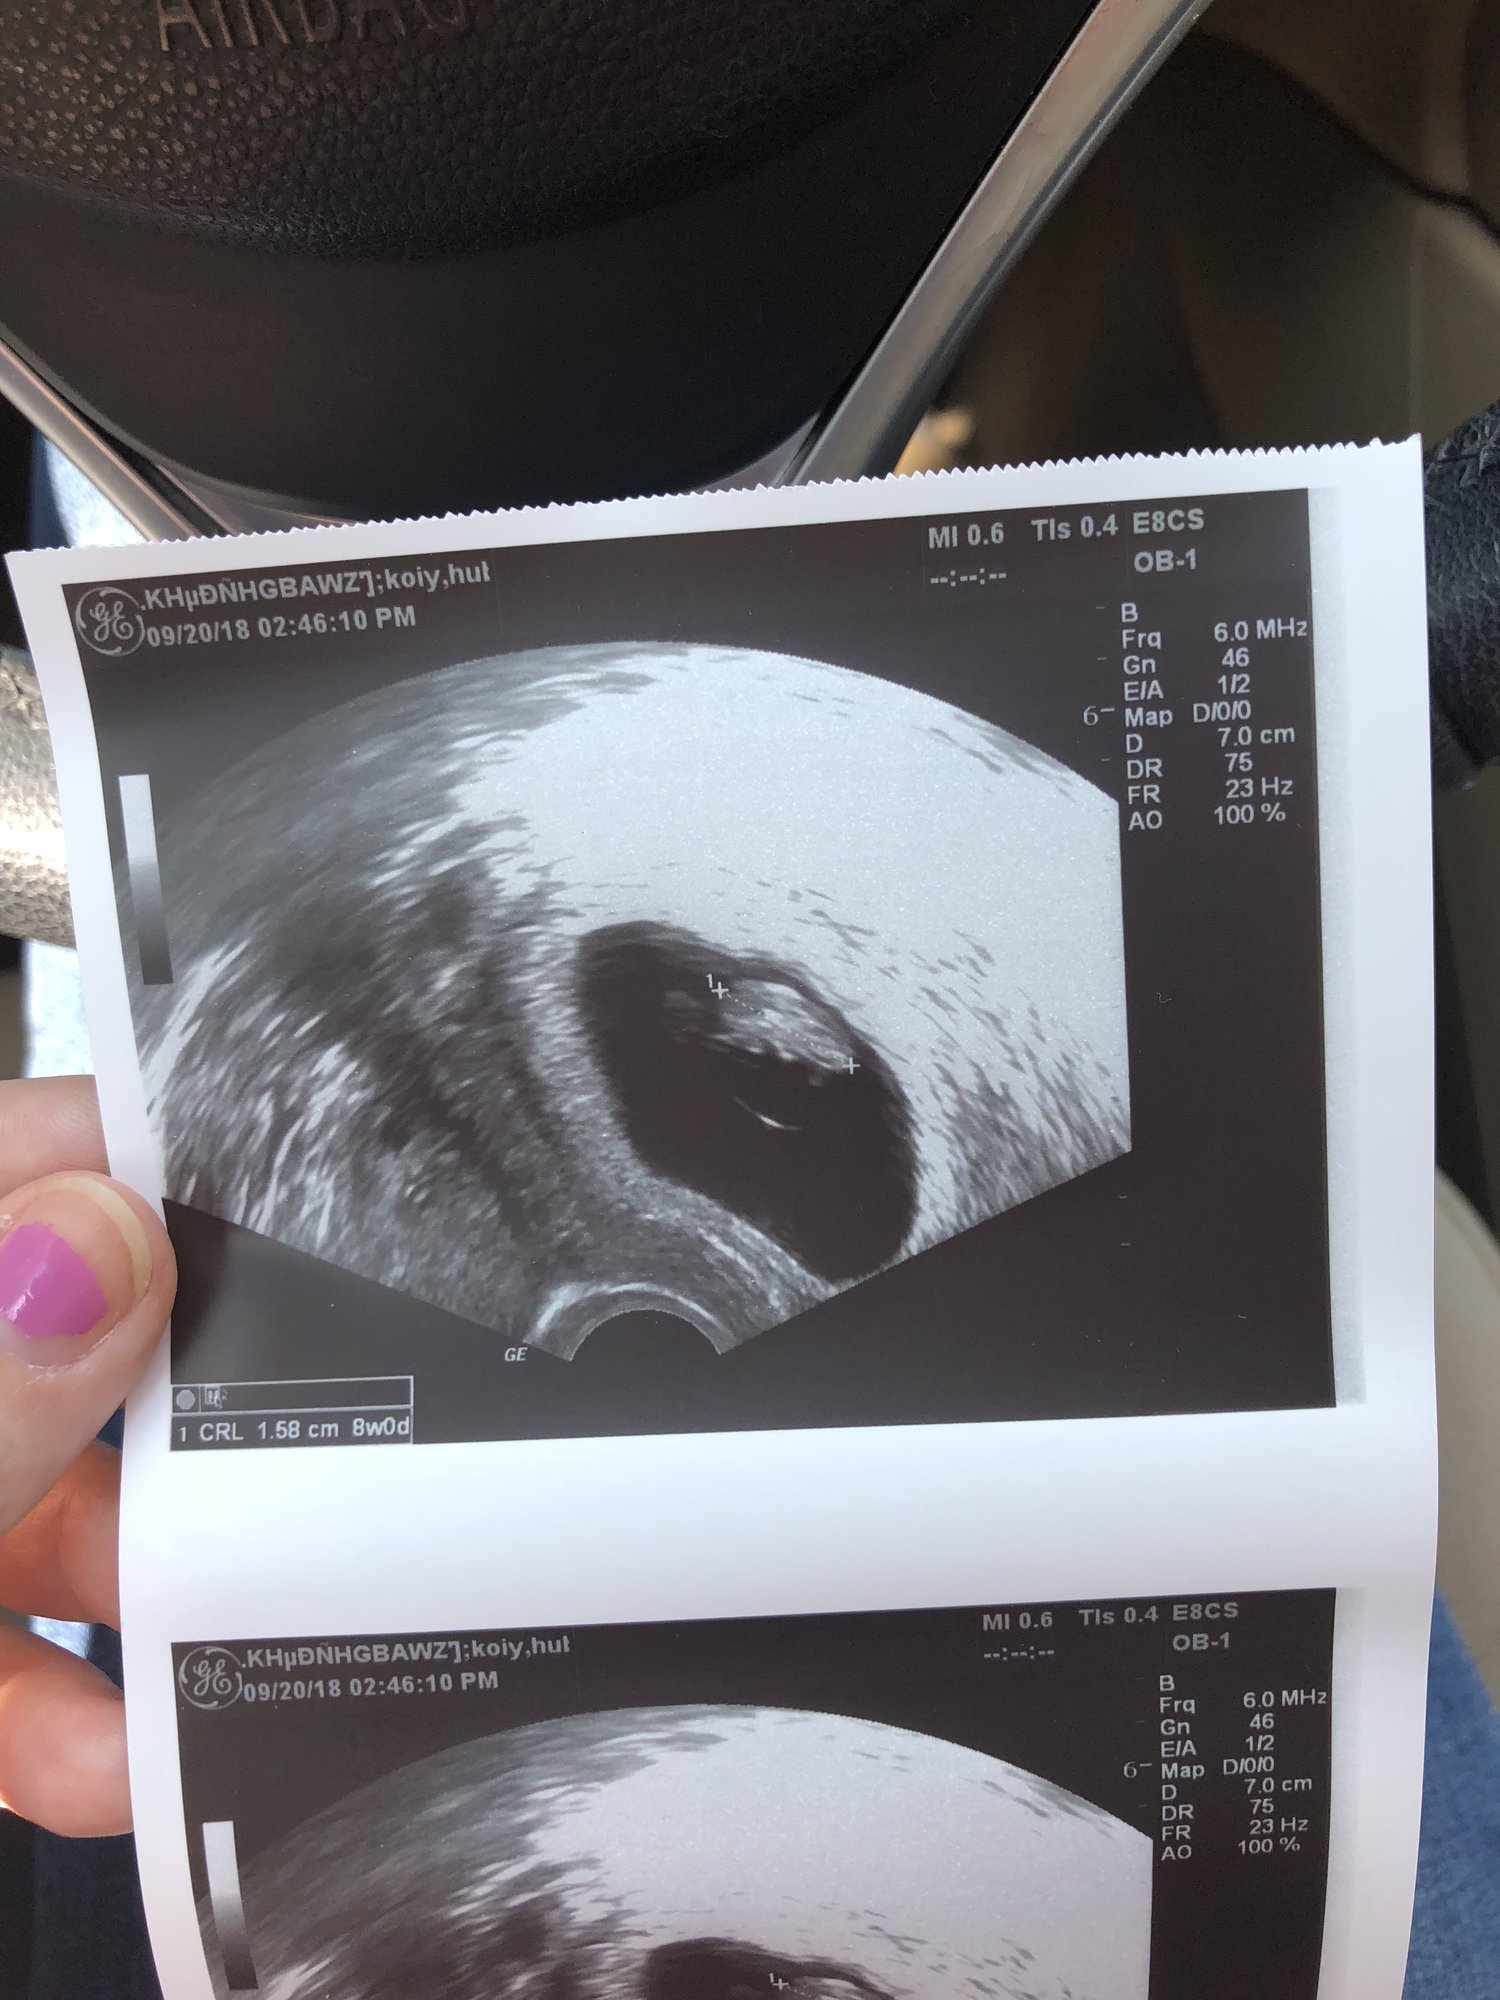

We had our first ultrasound today! We were estimating 6w1d today, and we measured that exactly! The pictures we got don’t show the baby very well because the US tech had measuring marks on them. She measured the heartbeat at 105. Such a relieving feeling seeing that little flicker!

Today was so hard for me. This was our big milestone ultrasound in my mind bc we’ve never gotten this far and I just went in fully expecting bad news. It really made me realize how effed up I am in the head from all of this. BUT. Everything was perfect. She even let us hear the heartbeat which was a surprise because they don’t normally do that at our practice and it was so much more amazing than I could have imagined it would be. And getting to see my husbands face when he heard it was just...sigh. Measuring 8 weeks exactly and working hard on those tiny arms and legs! I have two more with my RE and then pick right up with my OB after that, so grateful to not have a gap in care the time around!